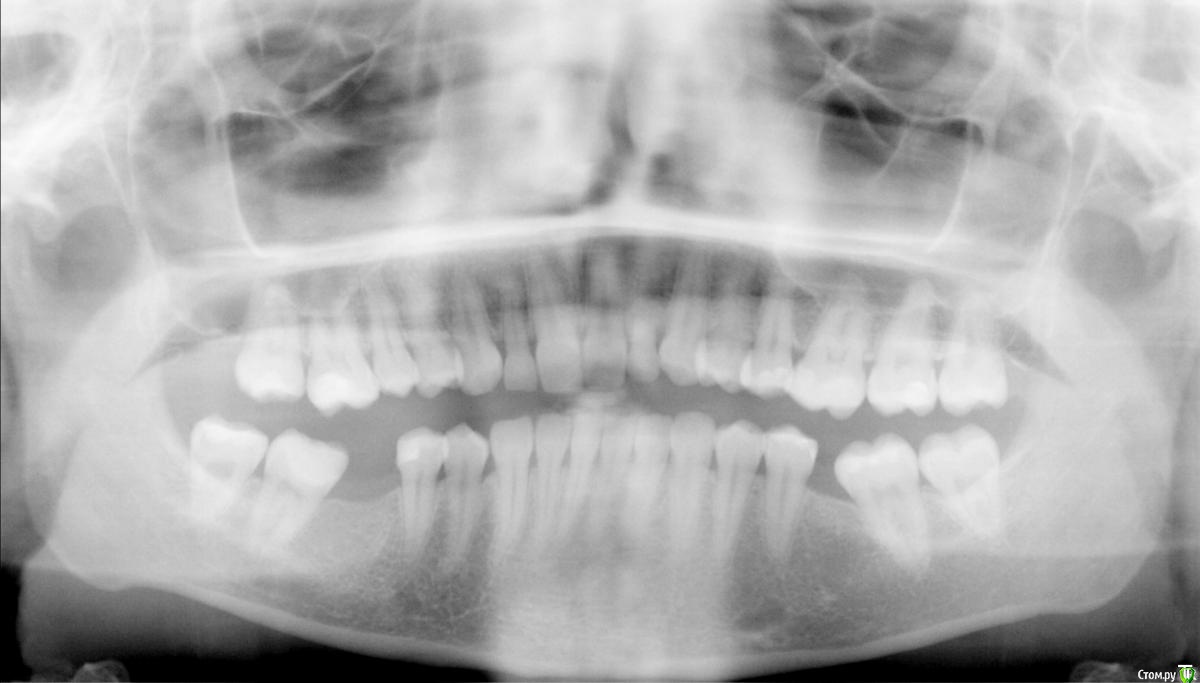

Посоветуйте пожалуйста лучшее решение в данной ситуации: дальние зубы стоят отдельно и наклонены, рядом зубы удалены больше 5 лет назад. Надо ли и как выпрямить зубы и потом поставить импланты для решения проблемы?снимок прикладываю